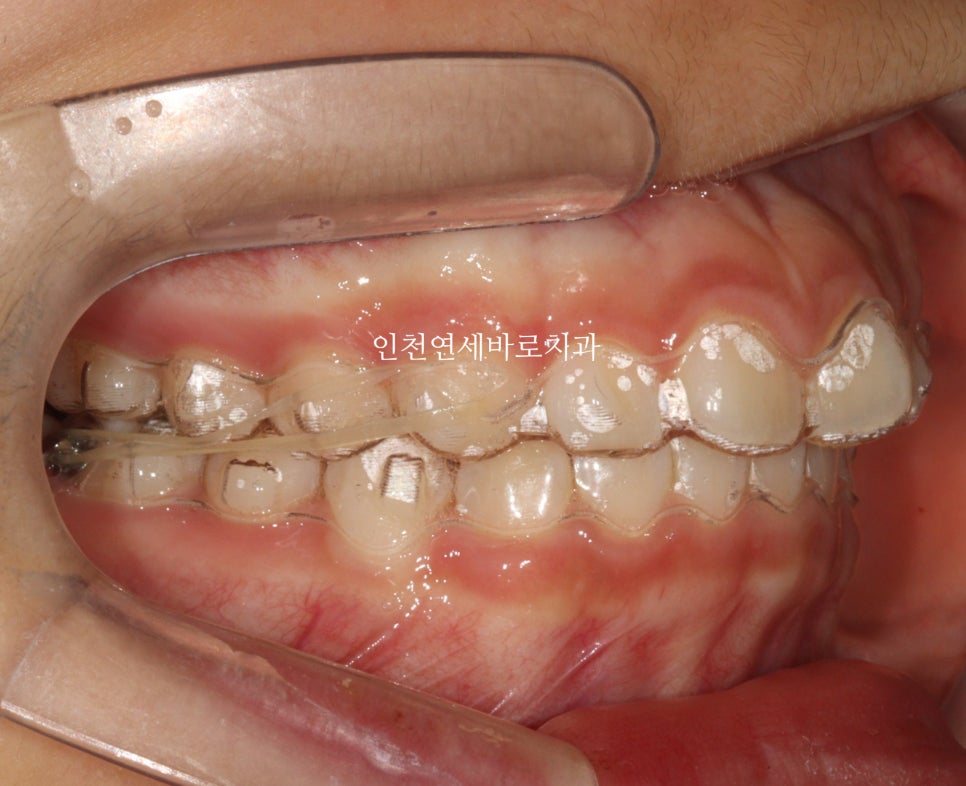

치료 전 상태 및 진단

인천연세바로치과에 온 환자아이입니다.

앞니가 튀어나와있고, 삐뚤삐뚤, 그리고

#과개교합

도 있는 아이었습니다.

| 초기 상태 | 앞니 돌출, 배열 불량, 과개교합 |